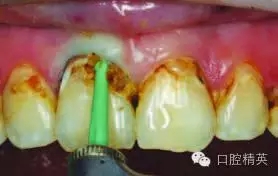

圖4:去除大量齲壞得牙本質(zhì)后

使用#6 Smartburs II車針( SSWhite)在轉(zhuǎn)速15,000轉(zhuǎn)每分鐘下開始去腐(圖3)。使用該車針去腐至該型號的車針頭部無法進(jìn)入較小的齲壞部位有效去腐(圖4)。

接下來使用#4 Smartburs II車針完成剩下的感染牙體組織的去腐操作(圖5)。